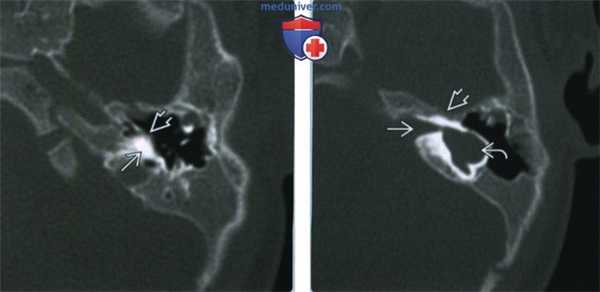

(Слева) На рисунке в аксиальной плоскости показаны признаки аплазии улитки, включая уменьшение внутреннего слухового канала (ВСК) с отсутствием улитковою нерва, улитки; с мальформацией преддверия и полукружного канала, уплощением переднею колена ЧH VII.

(Справа) При аксиальной МРТ SPACE у четырехмесячной девочки с врожденной НСТУ отсутствует улитка. Определяется глобулярная аномалия преддверия и горизонтального полукружного канала. В коротком и узком внутреннем слуховом канале находятся преддверный и лицевой нервы. Улитковый нерв не визуализируется.

(Слева) При аксиальной КТ в костном окне у этой же пациентки отсутствует улитка, определяется легкое уплощение мыса улитки.

(Справа) При аксиальной КТ в костном окне у этой же пациентки определяется глобулярная мальформация преддверия и горизонтального полукружною канала. Визуализируется короткий и узкий ВСК. Частично визуализируется переднее колено лицевого нерва, идущее под тупым углом, канал лицевого нерва имеет аномальный ход.